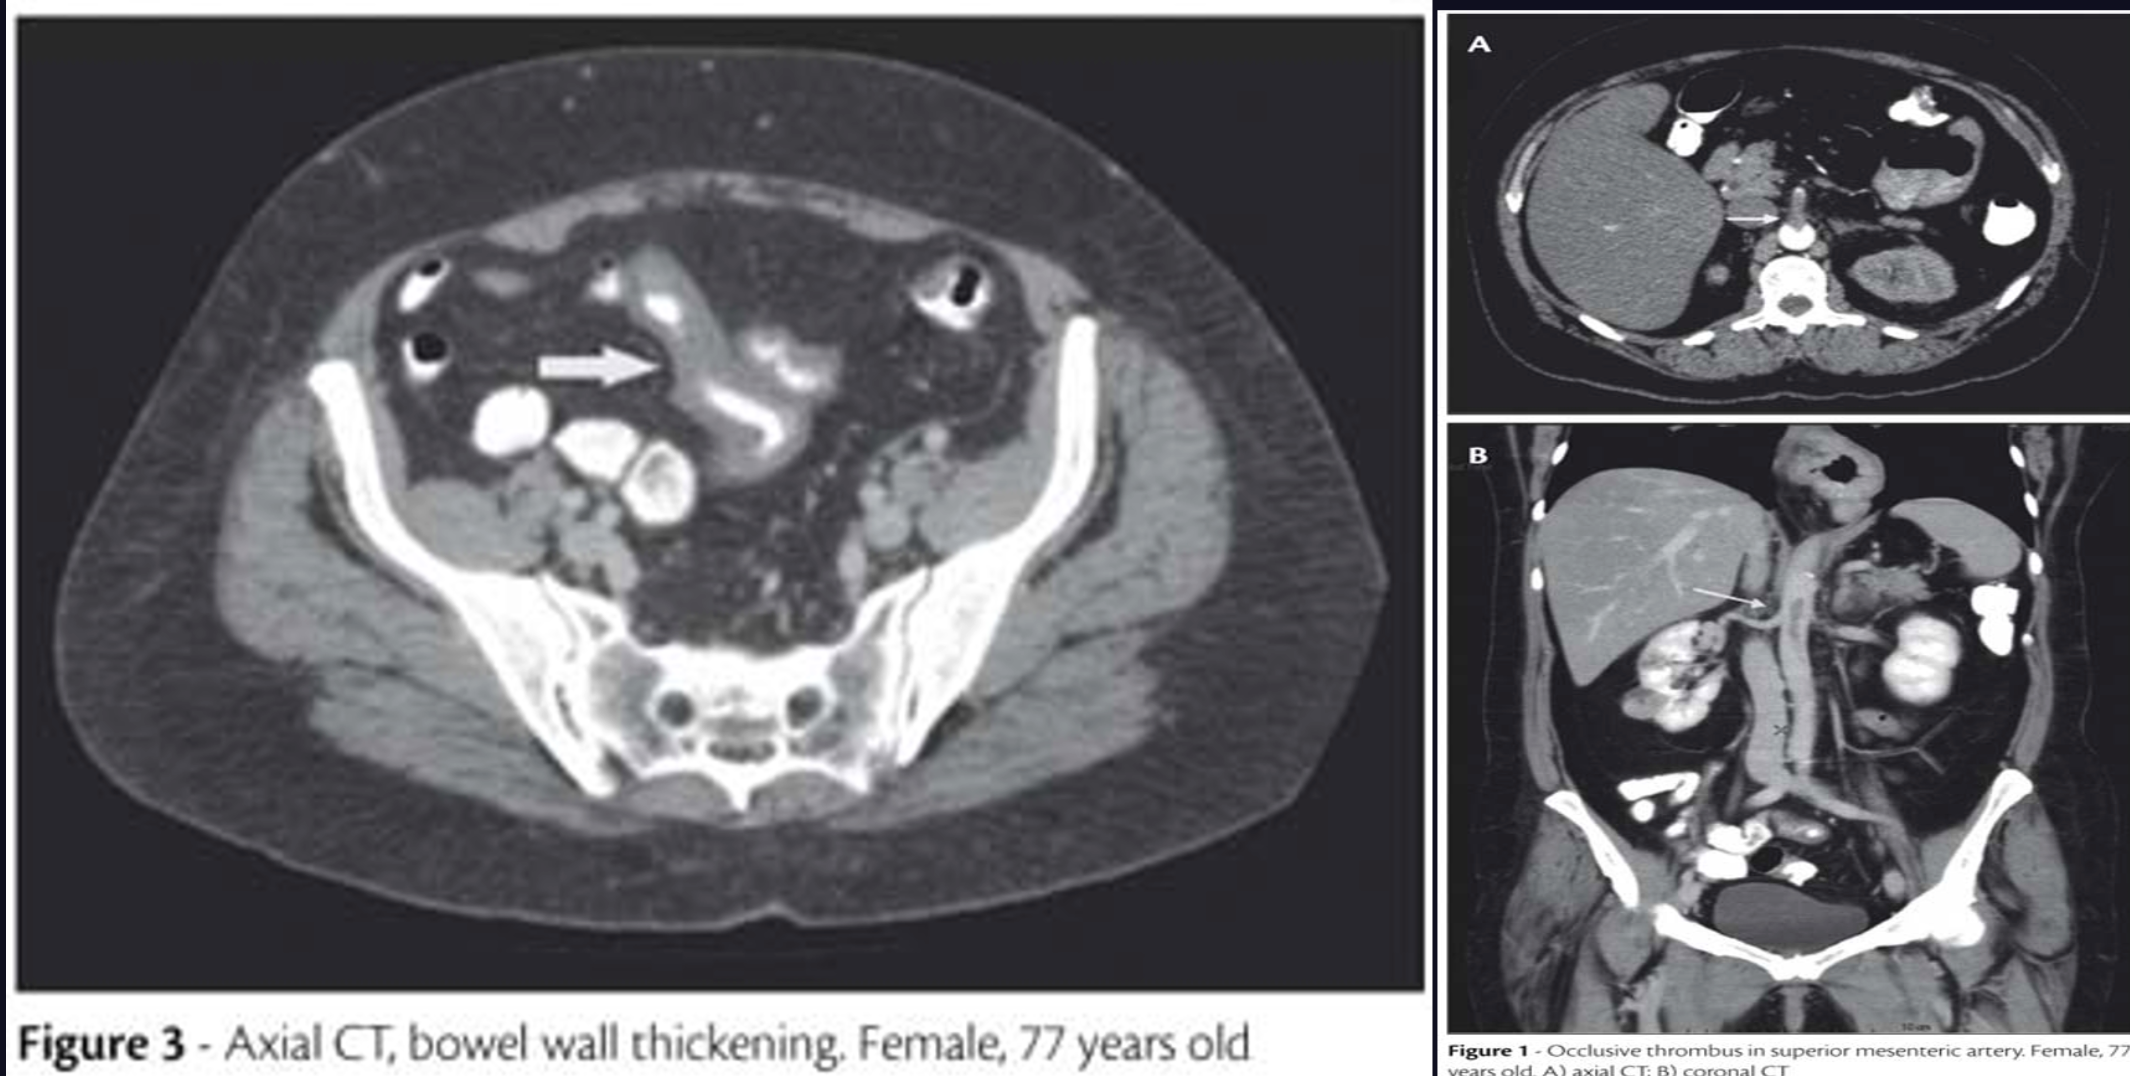

- CT angiography

- Assess mesenteric vasculature, intestine & its mesentery

- Test of choice for acute mesenteric venous thrombosis